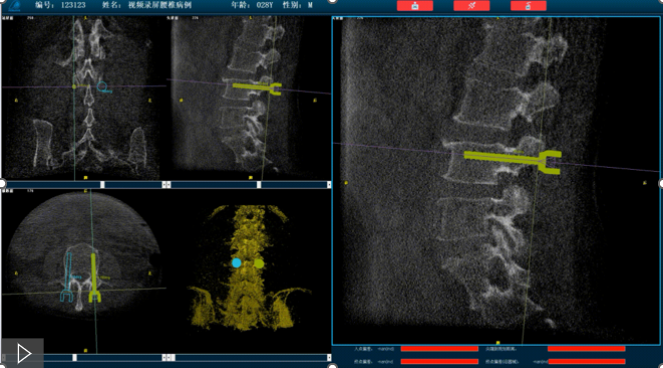

首先,需要明確的是機器人手術(shù),機器人在術(shù)中還是做輔助性操作,術(shù)前基于三維C形臂等影像掃描得到骨骼結(jié)構(gòu)的三維數(shù)據(jù),機器人系統(tǒng)利用手術(shù)規(guī)劃軟件,引導醫(yī)生進行可視化預手術(shù)規(guī)劃(釘?shù)酪?guī)劃、入釘角度),選擇合適的螺釘規(guī)格、尺寸,輔助評估和及時調(diào)整手術(shù)路徑規(guī)劃設計,整臺手術(shù)都是在主刀醫(yī)生的把控下進行操作的。機器人系統(tǒng)不僅靠譜,而且還提升了手術(shù)的安全性、機械臂的精準以及力傳感識別、實時動態(tài)追蹤等保護技術(shù),增加了手術(shù)的準確性和安全性。

就以普愛醫(yī)療骨科機器人PL300B為例,骨科機器人可以保證亞毫米級精準度,例如在脊柱上植入椎弓根螺釘,傳統(tǒng)手術(shù)需要暴露骨組織解剖結(jié)構(gòu),往往會有10-20cm的開口,而使用了手術(shù)機器人可以將開口轉(zhuǎn)變?yōu)閿?shù)個1-2cm的開口,出血量降低至95%以上,大大降低并發(fā)癥的發(fā)生率,同時有益于病患的更快的術(shù)后恢復。